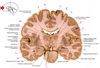

9

Q

a

Body of corpus callosum

10

b

septum pellucidum

11

c

Corona radiata

12

d

Anterior horn of lateral ventricle

13

e

Globus pallidus

14

f

Anterior commissure

15

g

Optic chiasm

16

h

Optic tract

17

i

Uncus

18

j

19

k

20

L

Putamen

21

m

Anterior limb of internal capsule

22

n

Head of caudate nucleus